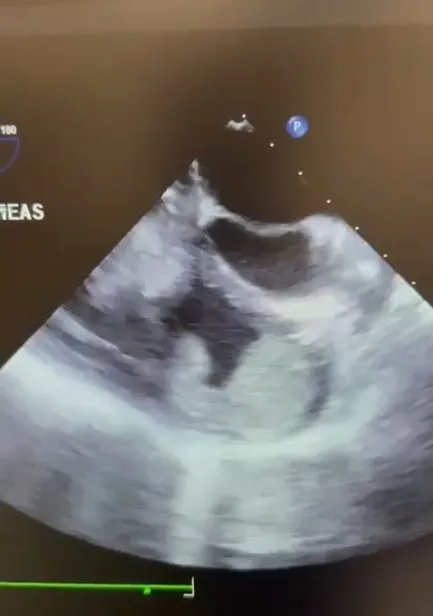

Nefes darlığı ve sırt ağrısı şikâyetleriyle Elazığ Fethi Sekin Şehir Hastanesi Acil Servisi'ne başvuran yabancı uyruklu 22 yaşındaki Mutemenna Necib'e yapılan tetkikler sonucunda pulmoner emboli tanısı konuldu. Embolinin kaynağını belirlemek amacıyla yapılan Bilgisayarlı Tomografi ve EKO incelemelerinde, kalbin neredeyse tamamını dolduran büyük bir kitle tespit edildi. Hayati risk taşıyan tablo üzerine hasta, Kalp ve Damar Cerrahisi Uzmanı Op. Dr. Sefa Şenol tarafından acil olarak değerlendirmeye alındı. Yapılan değerlendirmelerin ardından Op. Dr. Sefa Şenol ve Doç. Dr. Davut Azboy'un yer aldığı ekip tarafından hasta vakit kaybedilmeden ameliyata alındı. Hastalığa özgü cerrahi yöntemler eşliğinde gerçekleştirilen açık kalp ameliyatında, kalp içerisindeki kardiyak kitle tamamen çıkarıldı. Yaklaşık 2 saat süren operasyon başarıyla tamamlanırken, ameliyat sonrası yoğun bakım ve servis süreçleri sorunsuz şekilde ilerledi. Tedavisi başarıyla tamamlanan Mutemenna, taburcu edildi. Gerçekleştirilen operasyon, Elazığ Fethi Sekin Şehir Hastanesi'nin ileri düzey kalp cerrahisi alanındaki yetkinliğini bir kez daha ortaya koydu.

Operasyonu gerçekleştiren ve hastanın durumu hakkında tıbbi detayları paylaşan Op. Dr. Sefa Şenol, vakanın ciddiyetini ve operasyon sürecini şu sözlerle ifade etti, "Hastamız nefes darlığı ve sırt ağrısı şikayetleri ile Fethi Sekin Şehir Hastanesi acil kliniğine başvurdu. Burada yapılan incelemelerde pulmoner embolisi olduğu görüldü. Pulmoner embolisi gerekçesiyle Göğüs Hastalıkları yatışı uygun gördü. Sonra ana sebebi öğrenebilmek için çekilen EKO ve bilgisayarlı tomografisinde; özellikle kalbin sağ atriyum ve sağ ventrikülün içerisini hemen hemen dolduran, buradan da sol atriyuma uzanan, yani kalbinin dört odacığı bulunmaktadır, bu üç odacığı da invaze eden bir kitle olduğu görüldü. Hastamızı hemen acil bir şekilde farklı bir konseptte operasyona aldık. Operasyon sonrası yaklaşık 1-2 saat sürdü operasyonumuz. Hastamız sonra yoğun bakıma saatli bir şekilde alındı. Bugün de taburcu edeceğiz. Aldığımız kitleyi de patolojiye gönderdik. Sonucuna göre haberleşeceğiz. Hastamız bundan sonra bizim takibimizde olacak"